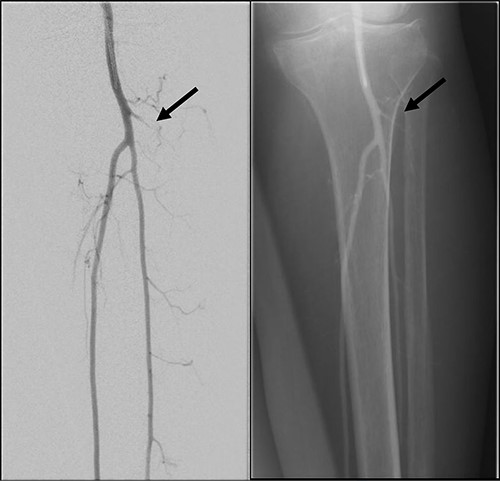

Good arterial flow of the ATA (arrow) after successful angioplasty and stenting.

Arterial flow noted at distal ATA and dorsalis pedis artery (arrow) after successful angioplasty and stenting.